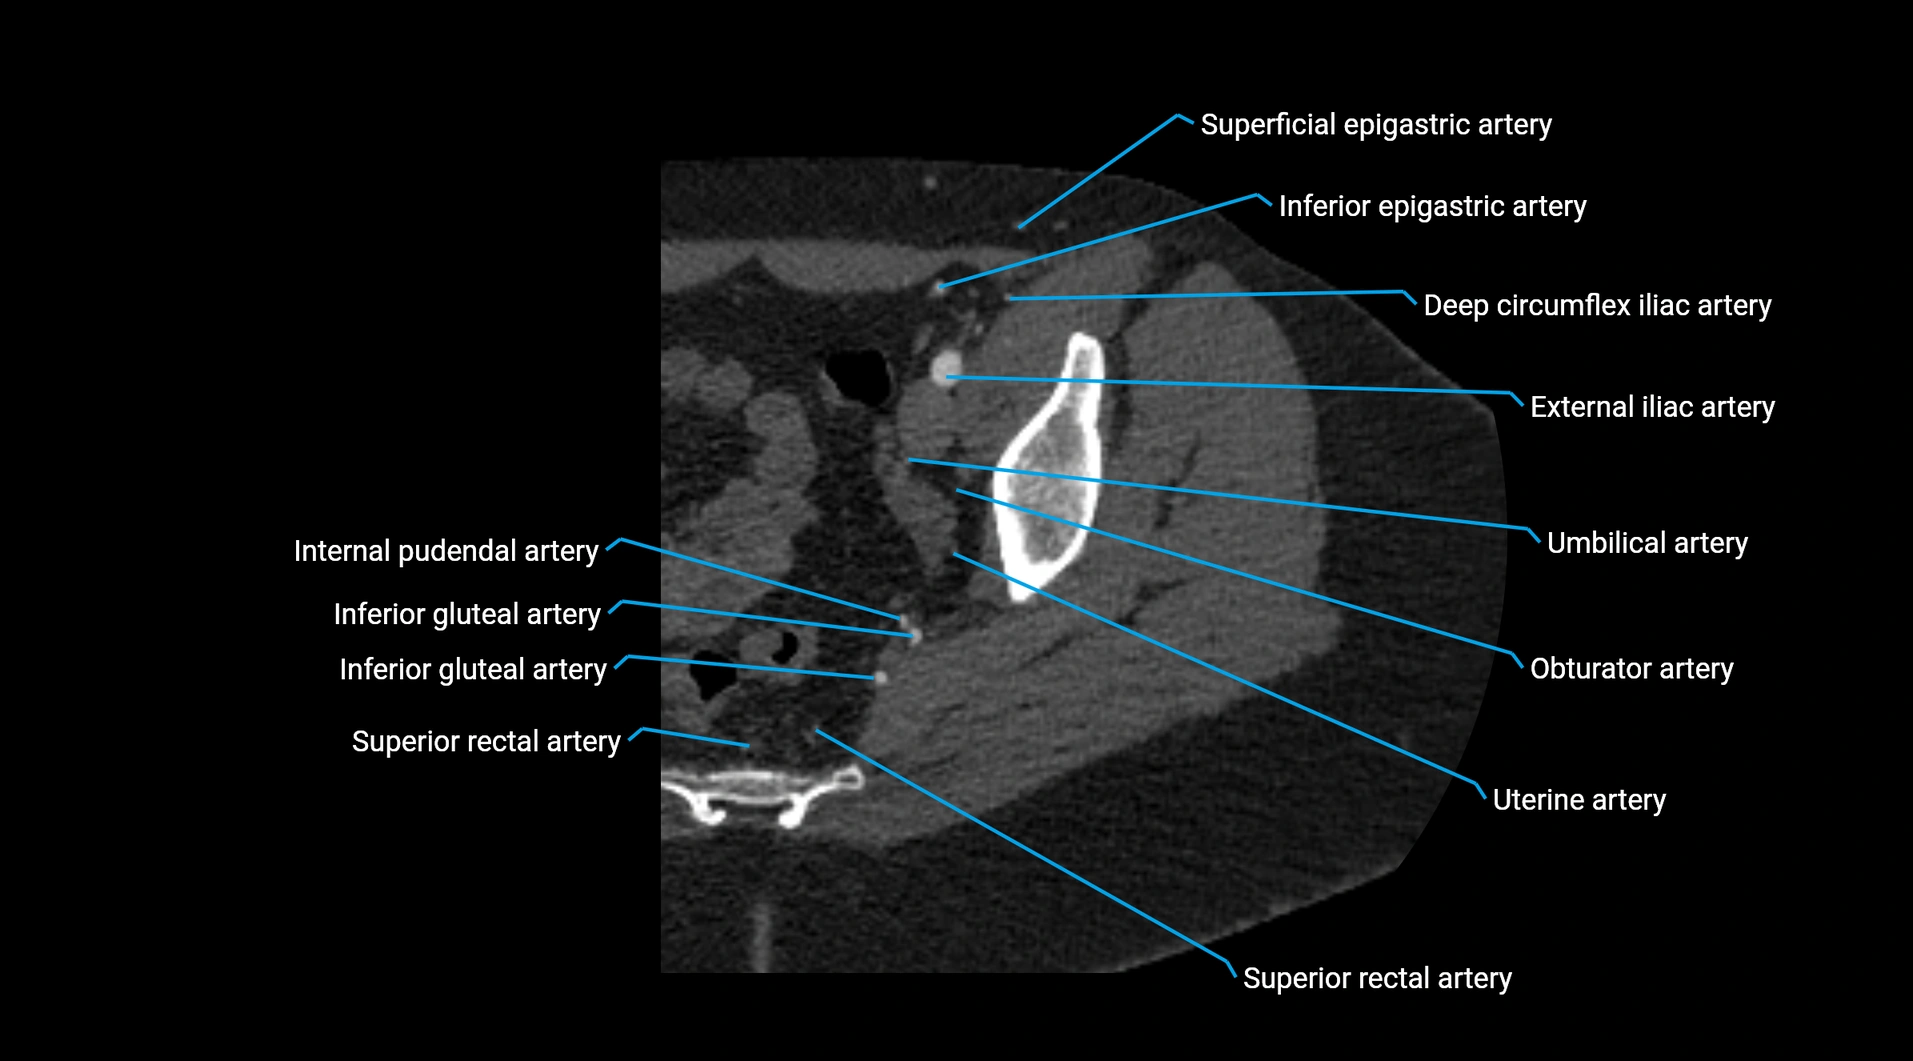

Branches

• Unpaired visceral branches: celiac trunk, superior mesenteric artery (SMA), inferior mesenteric artery (IMA)

• Paired visceral branches: middle suprarenal arteries, renal arteries, gonadal arteries (testicular or ovarian)

• Parietal branches: inferior phrenic arteries, lumbar arteries, median sacral artery

• Terminal branches: right and left common iliac arteries

CT Appearance

Contrast-enhanced CT (CTA):

• Gold standard for abdominal aortic imaging

• Provides excellent detail of lumen, wall, aneurysm, thrombus, and branch vessels

• Multiplanar and 3D reconstructions help in aneurysm measurement, stent graft planning, and dissection evaluation

• Detects acute rupture, traumatic injury, or occlusion with high sensitivity